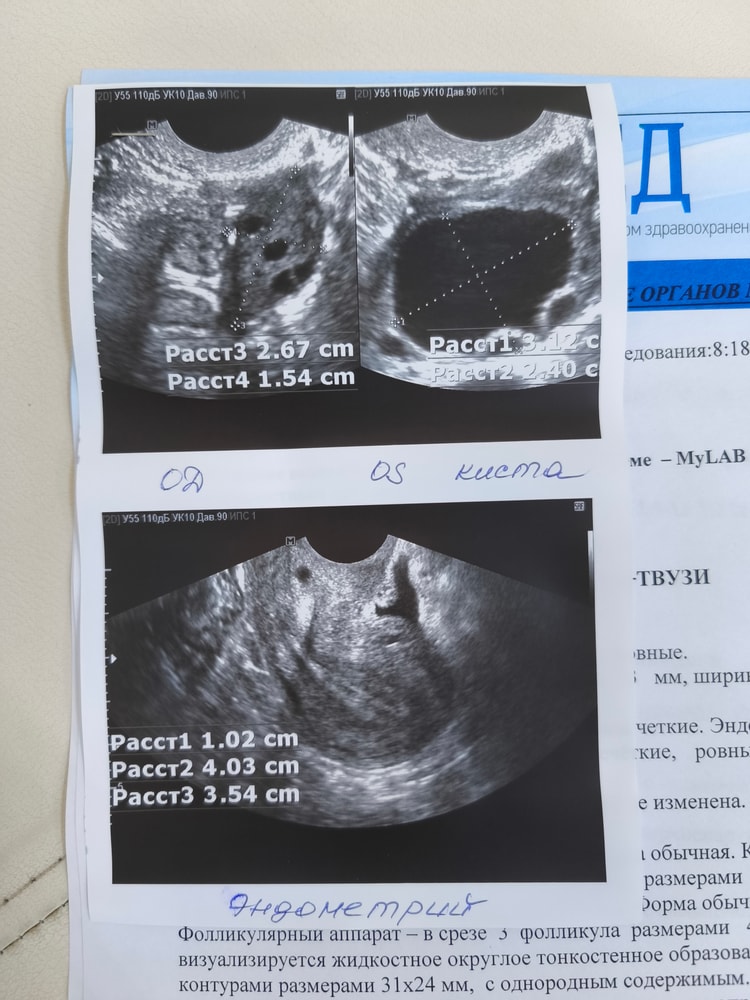

Фолликулярная киста! 🤬

Собираю анализы на перенос и офигела - по гормонам какая-то лажа, а на УЗИ фоллик. киста! Эндометрий толстенный - 10 мм, как будто 2я фаза ещё не кончилась

Откуда взялась, непонятно 🤯 перед тем, как начать принимать утрик, была на УЗИ - доминантного не было, эндик 7мм. Как так то????